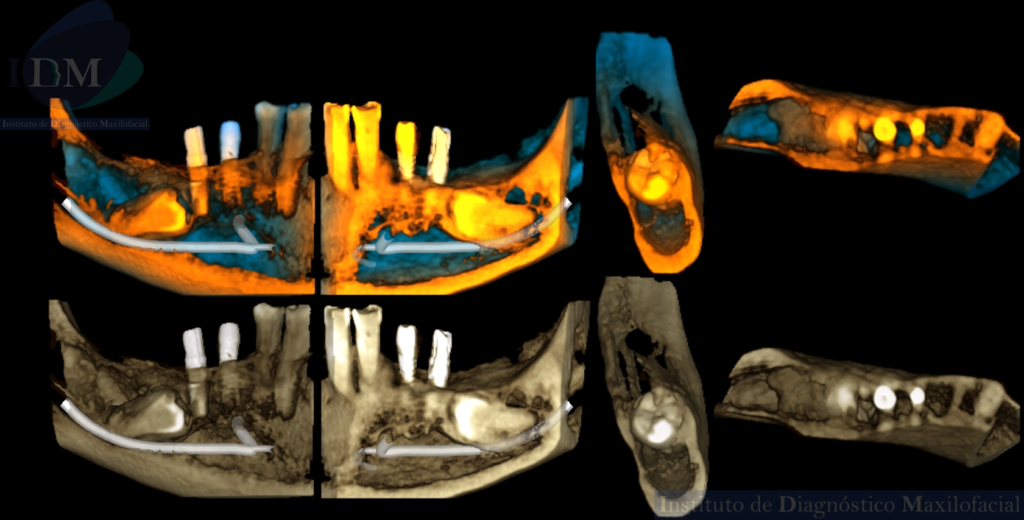

RECONSTRUCCIÓN 3D

A la evaluación de la radiografía panorámica se evidencia reabsorción ósea alveolar bimaxilar, edéntulo parcial bimaxilar y presencia de múltiples implantes con prótesis sobre implantes así como tratamientos restaurativos. Siendo lo más destacado una molar retenida en cuerpo mandibular izquierdo, la cual esta mesioangulada.

Siendo así que en la tomografía volumétrica de haz cónico se evidencia una hipercementosis radicular, con los segmentos radiculares contactando con el conducto dentario inferior. Finalmente se evidencia un borramiento del espacio del ligamento periodontal compatible con anquilosis dentaria.